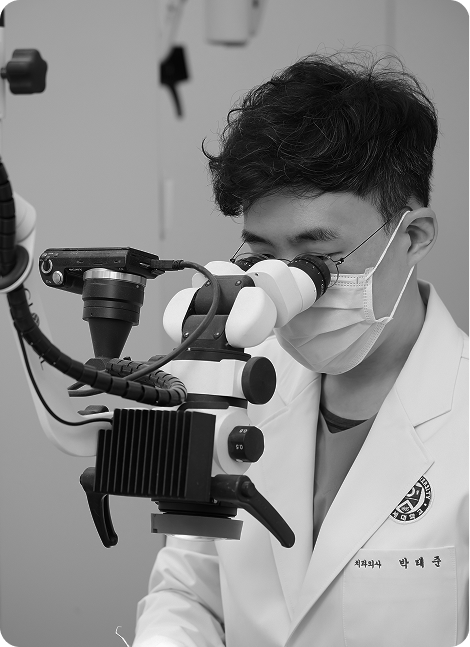

자연치아를 살리는 골든타임,

바로 지금입니다.

자연치아 하나의 가치는 3천만 원 이상,

빠르게 조치할수록 살릴 수 있는 확률은 올라갑니다.

통합치의학과 전문의 대표원장이 시작부터 끝까지 맞춤케어 해드리겠습니다.